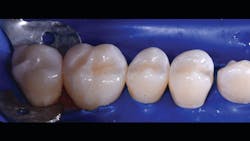

The final piece of the puzzle is the composite materials. In this case, Filtek One Bulk Fill Restorative (3M) and Filtek Bulk Fill Flowable Restorative (3M) were used. Bulk filling is more time efficient, technically simpler, and creates a monolithic form. Manipulation of composites and layering is known for a higher incidence of voids and defects. This case demonstrates the method of injection molding, which has the ability to create strong, monolithic, void-free, ideally contoured, mirror-finish restorations. Significant time savings occurs with simpler finishing requirements. Excess composite at the mid buccal, lingual, and occlusal areas is quickly reshaped with a disc. The subgingival area is then finished with a finishing strip. Finally, it’s time to finish and polish using a diamond-impregnated rubber polisher.

Just as Tofflemire bands, wooden wedges, and amalgam were suited for one another, anatomic matrices, wedges, separators, and flowable and bulk fill composites work harmoniously to create ideal posterior composite restorations that are strong, monolithic, and anatomic.

In the following case study (figures 1–11), the techniques and methods discussed will be demonstrated with the treatment of a quadrant of four posterior restorations. Four interproximal smooth-surface carious lesions are conservatively treated with two nonretentive saucer preparations and two marginal ridge-preserving opportunistic preparations.